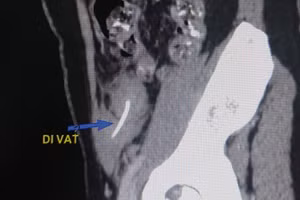

GD&TĐ - Nữ bệnh nhân 36 tuổi bị sưng đau vùng chậu bẹn. Các bác sĩ phát hiện có xương cá đi xuyên ống tiêu hóa ra ngoài thành bụng, đây cũng chính là lý do người phụ nữ bị đau bụng suốt 2 tuần.